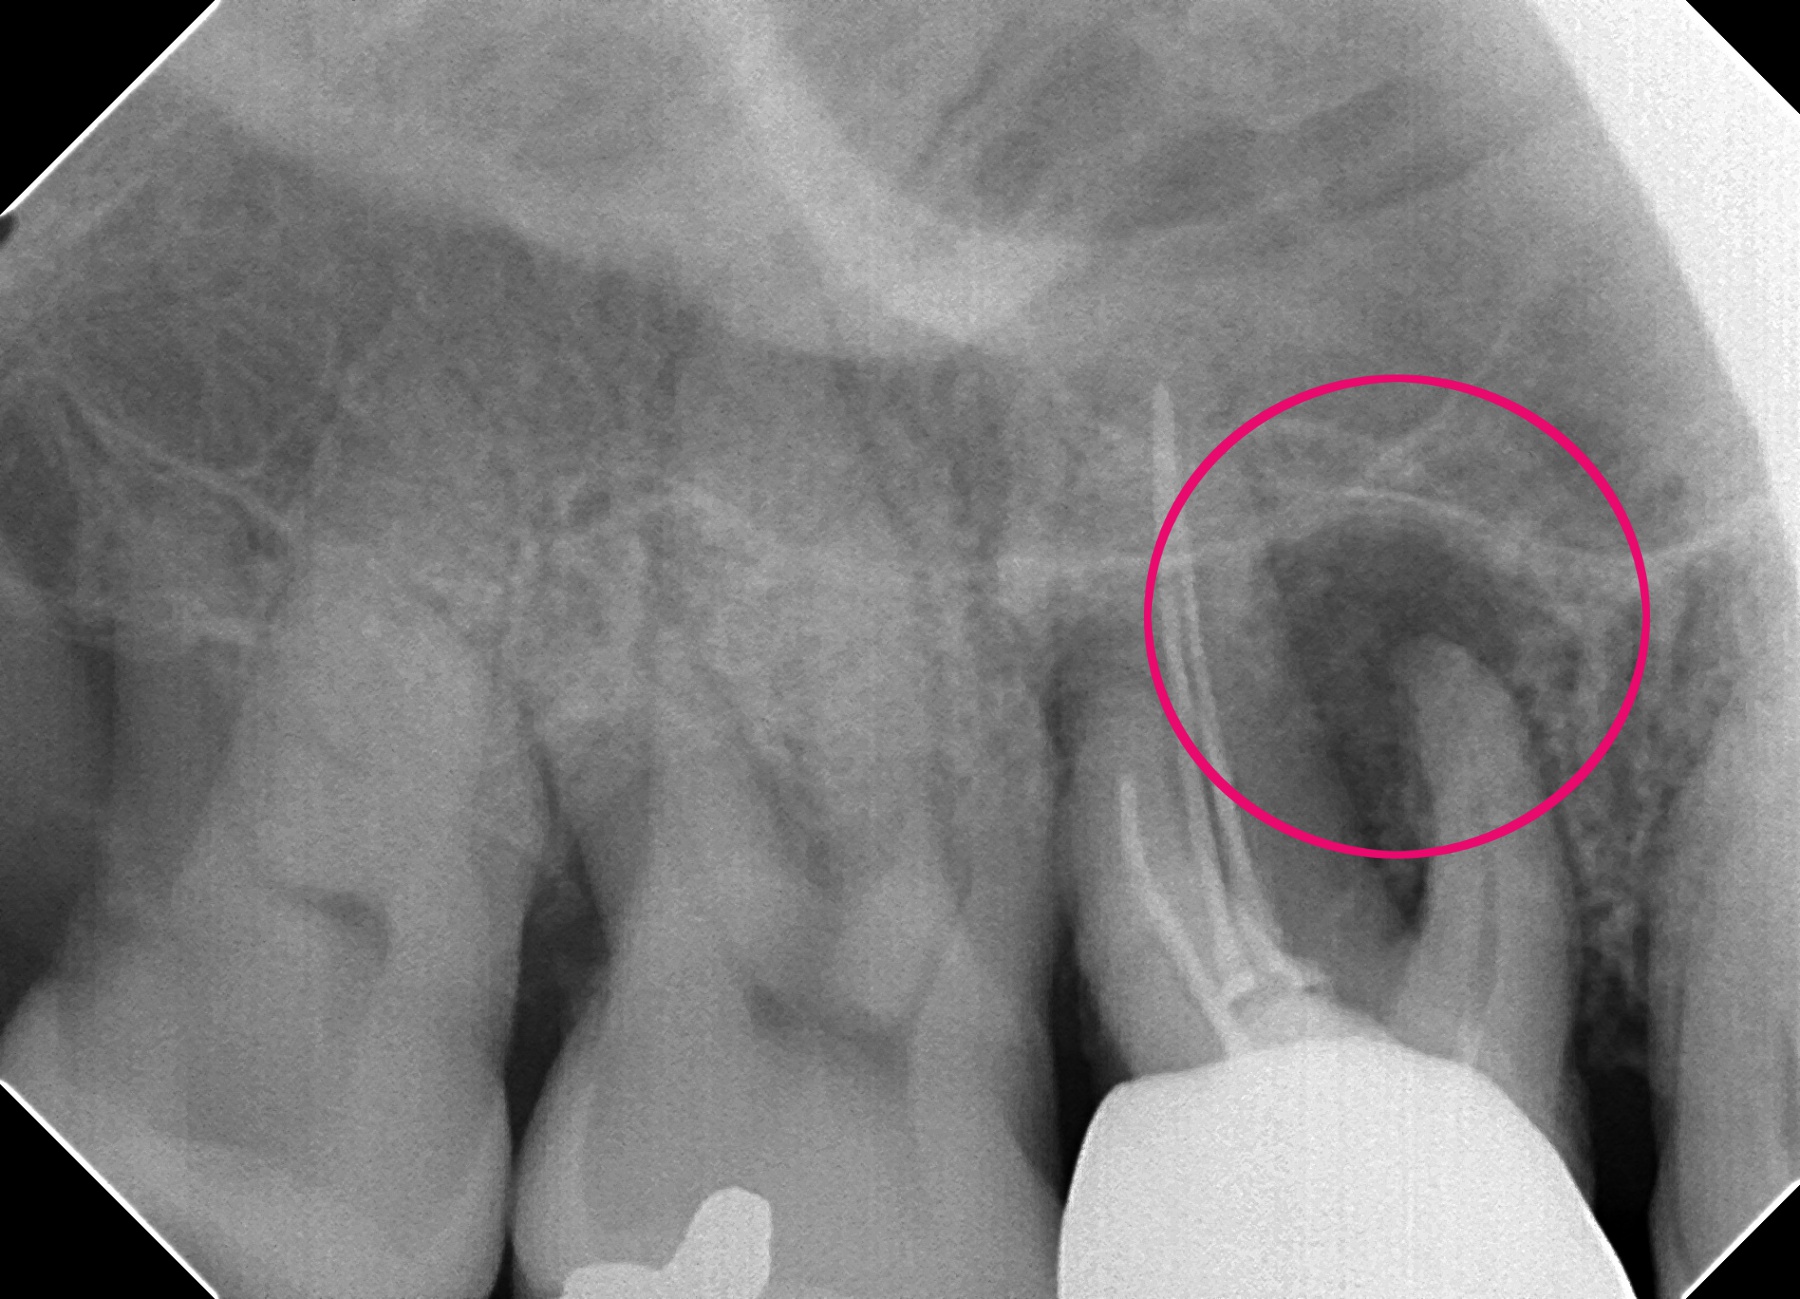

歯の根の先にうみが貯まり、レントゲンに黒く映っています。

根の先が菌に感染してうみが貯まると、うずいたり、痛みが出る可能性があります。

(他院で以前治療した歯の根の先が腫れた。)

うみを神経の通っていた管を通して出し管を消毒します。

管がきれいになったら根の先まで蓋をする薬をいれ、再び菌が入って感染するのを防ぎます。当医院では根の治療の回数や時間をかけますが、一本一本確実な治療を心がけています。